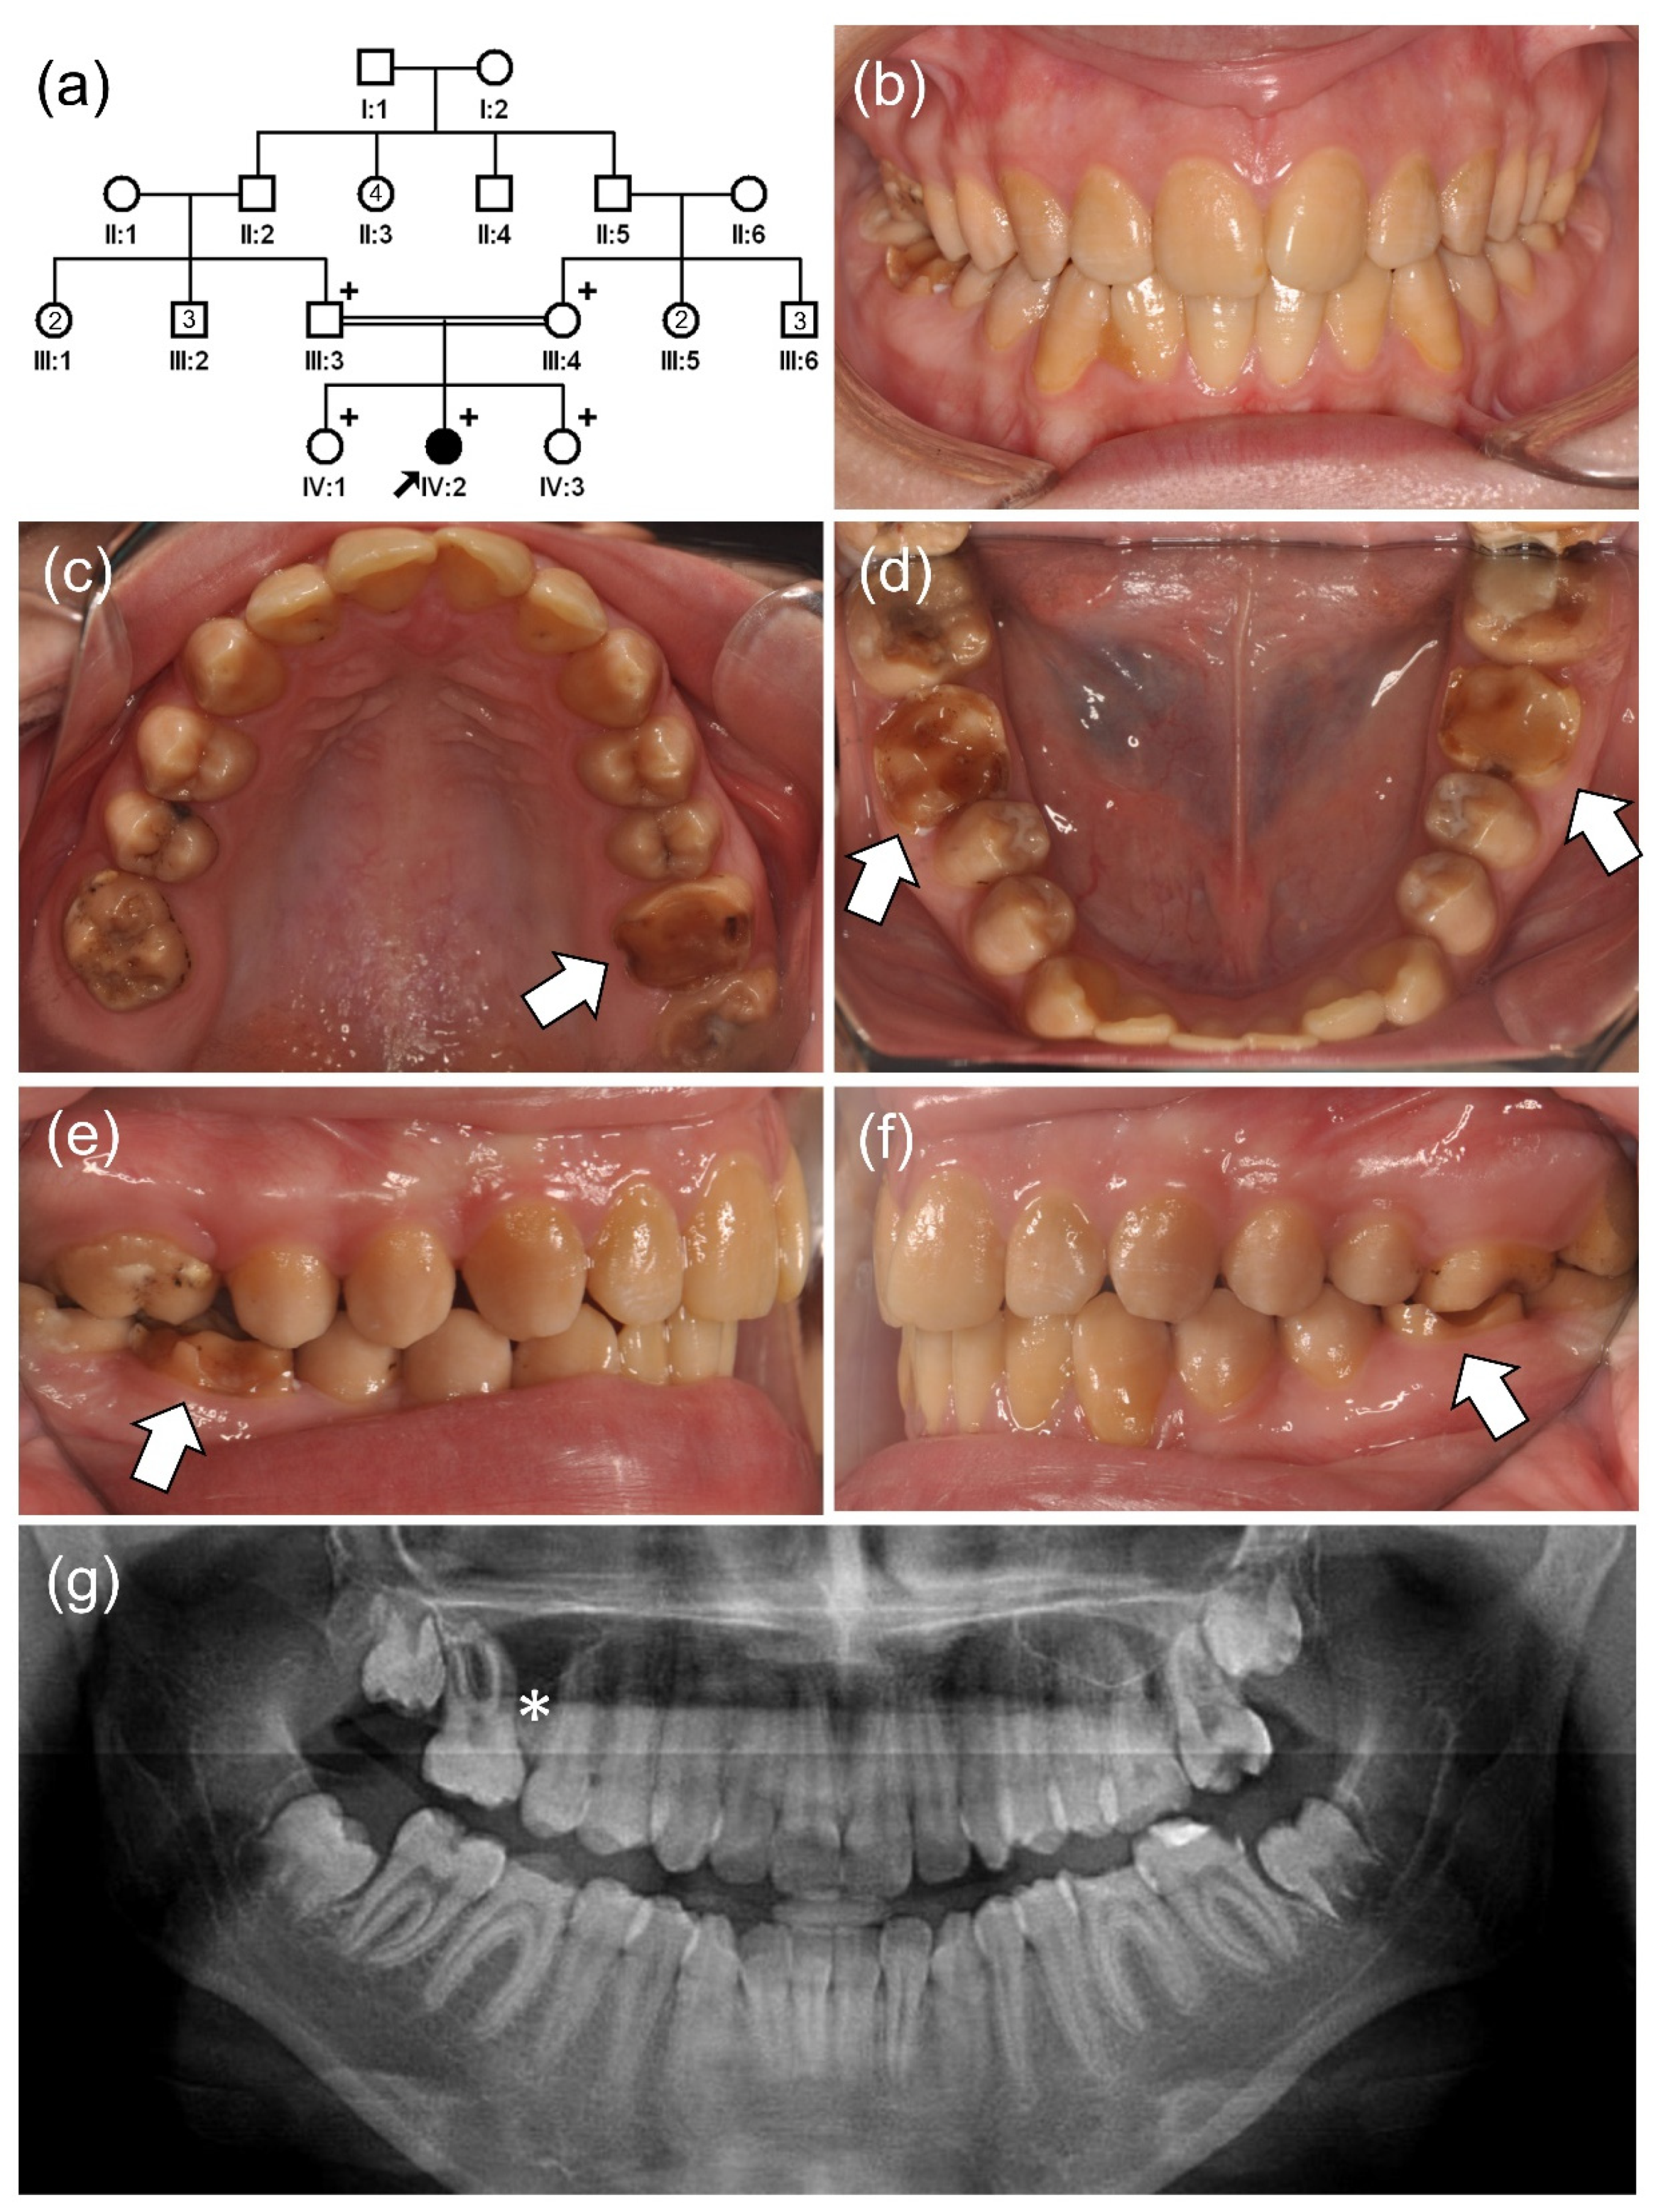

3.1. Family 1~3

3.2. Family 4